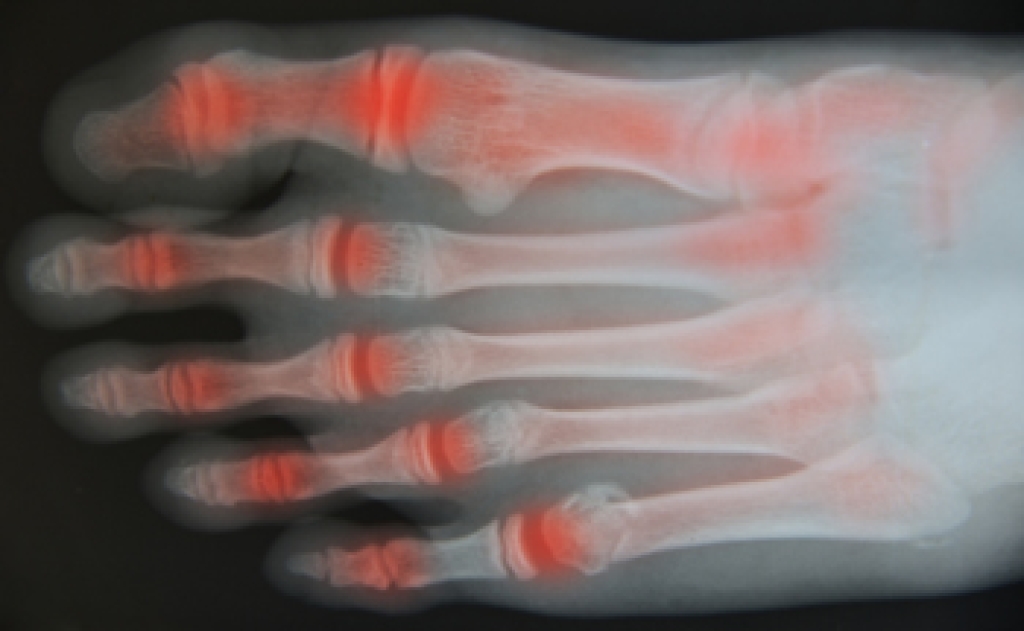

Arthritis is a joint disorder that involves the inflammation of different joints in your body, such as those in your feet. Arthritis is often caused by a degenerative joint disease and causes mild to severe pain in all affected areas. In addition to this, swelling and stiffness in the affected joints can also be a common symptom of arthritis.

Osteoarthritis is a disease that often targets people as they get older. What happens is that the cartilage between the joints wears down, removing the cushion between the bones and causing them to touch. This brings intense pain and can cause damage to the bones. In some cases of osteoarthritis, bumps known as Herberen’s and Bouchard nodes form at the joints, particularly in the fingers and toes. There is no cure for osteoarthritis, which is also a progressive disease, and the cause is unknown. In some cases, it is brought on by other conditions, including nervous system disorders, a buildup of certain minerals in the body, congenital diseases, and bone disorders. Treatment is available for osteoarthritis ranging from non-steroidal anti-inflammatory medication and topical creams that help reduce pain to surgery that replaces the cartilage or the joint itself. If you believe you have osteoarthritis that is affecting your feet and ankles, please see a podiatrist for treatment options.